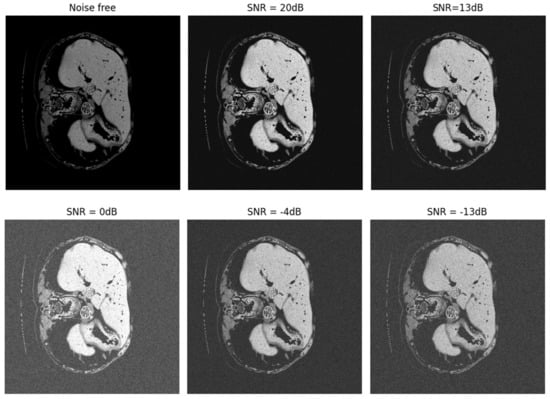

- Evaluation of the proposed network in noisy environments and maintaining the algorithm’s stability for various SNRs.